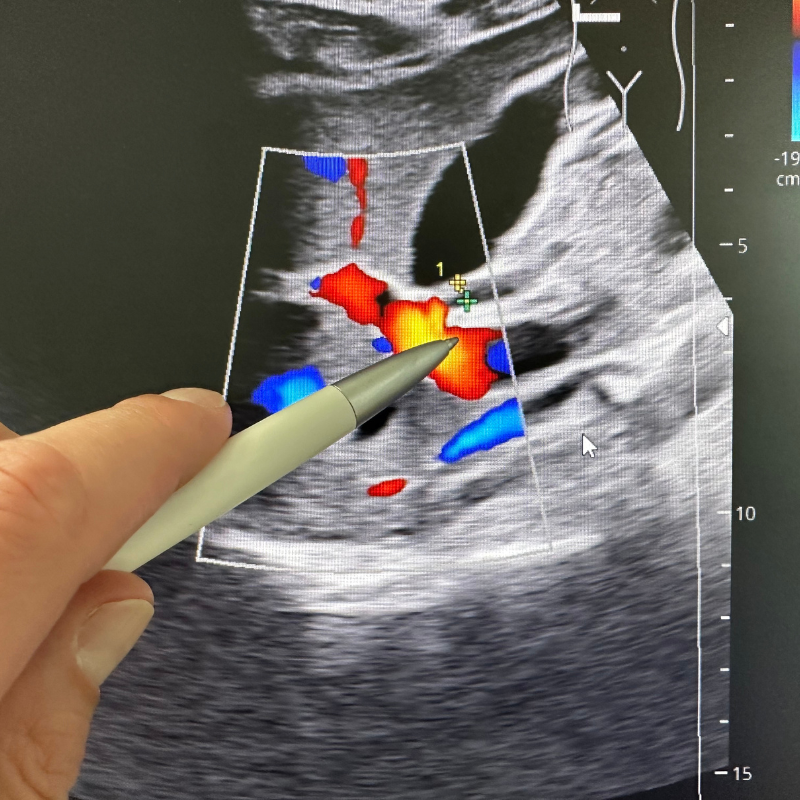

🔹4. Doppler Ultrasound